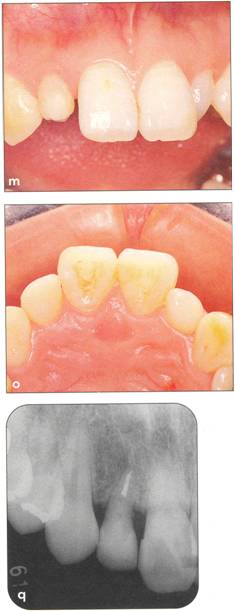

Fi 545e45f g 5-71 Three months after transplanta. tion. Notice the dark appearance of the crown. |

Fi 545e45f g 5-7m After bleaching of the transplant. ed tooth. |

Fi 545e45f gs 5-7n and 5-70 Composite resin res. toration of the transplanted tooth. |

Fi 545e45f g 5-7p Fi 545e45f ve months after transplantation. |

Fi 545e45f g 5-7q Three years after transplantation. |